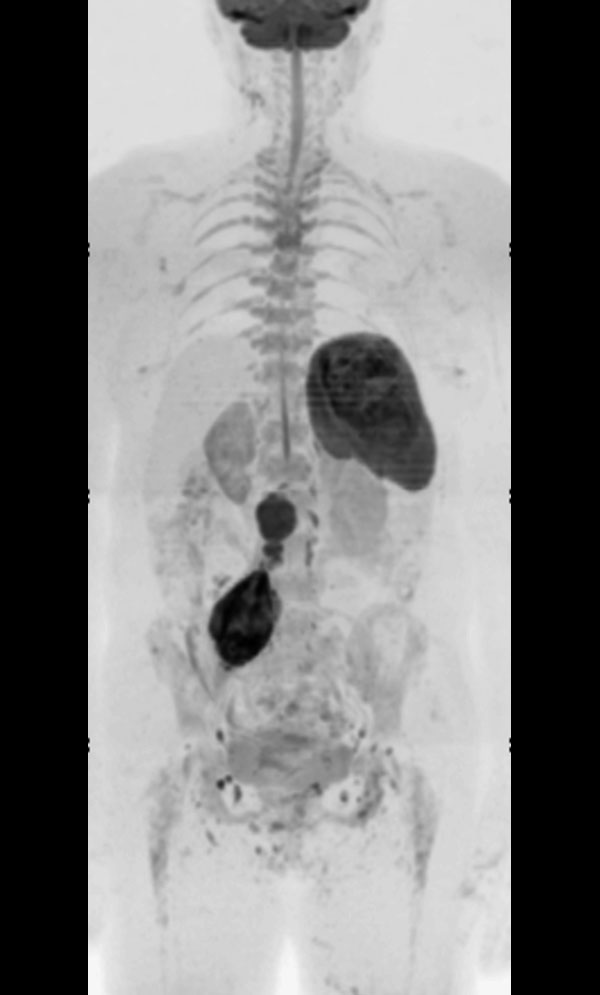

T2w STIR